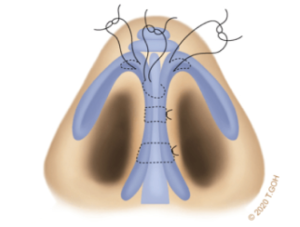

Choosing to combine the intricate skills of microsurgery with aesthetic surgery, Dr Goh specialises in gynaecomastia, surgery of the Asian face, particularly Asian eyelid surgery and rhinoplasty.

Blending the precision of microsurgery with the artistry of aesthetic surgery, Dr Goh has a special interest in gynaecomastia, facial procedures, including ptosis and eyelid surgery, as well as rhinoplasty.